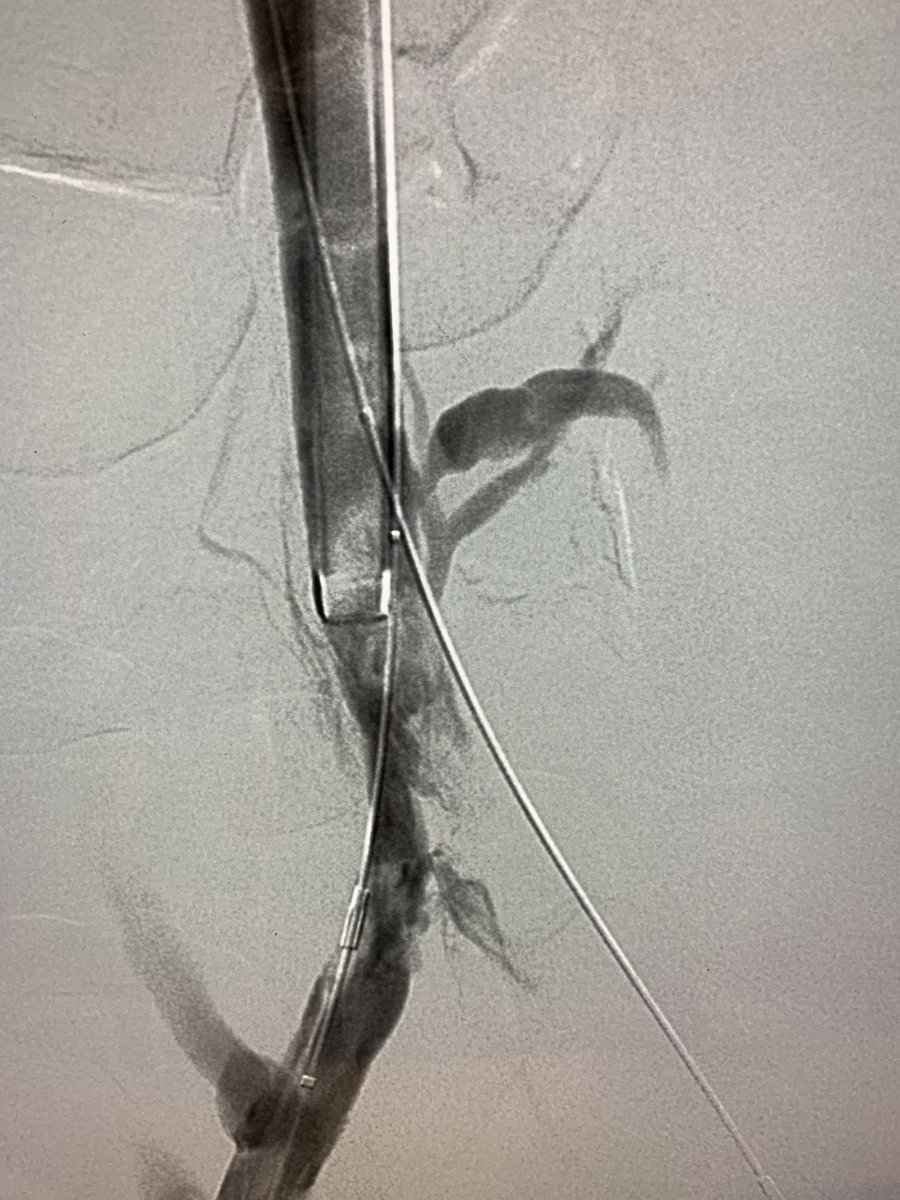

Forceps delivery of a tilted and embedded Argon Option Elite #IVCFilter. The key move here was using the forceps to free the filter apical tissue cap from the caval wall and some serious 🖐🏼 strength! #iRad #FilterOUT #FilterFriday